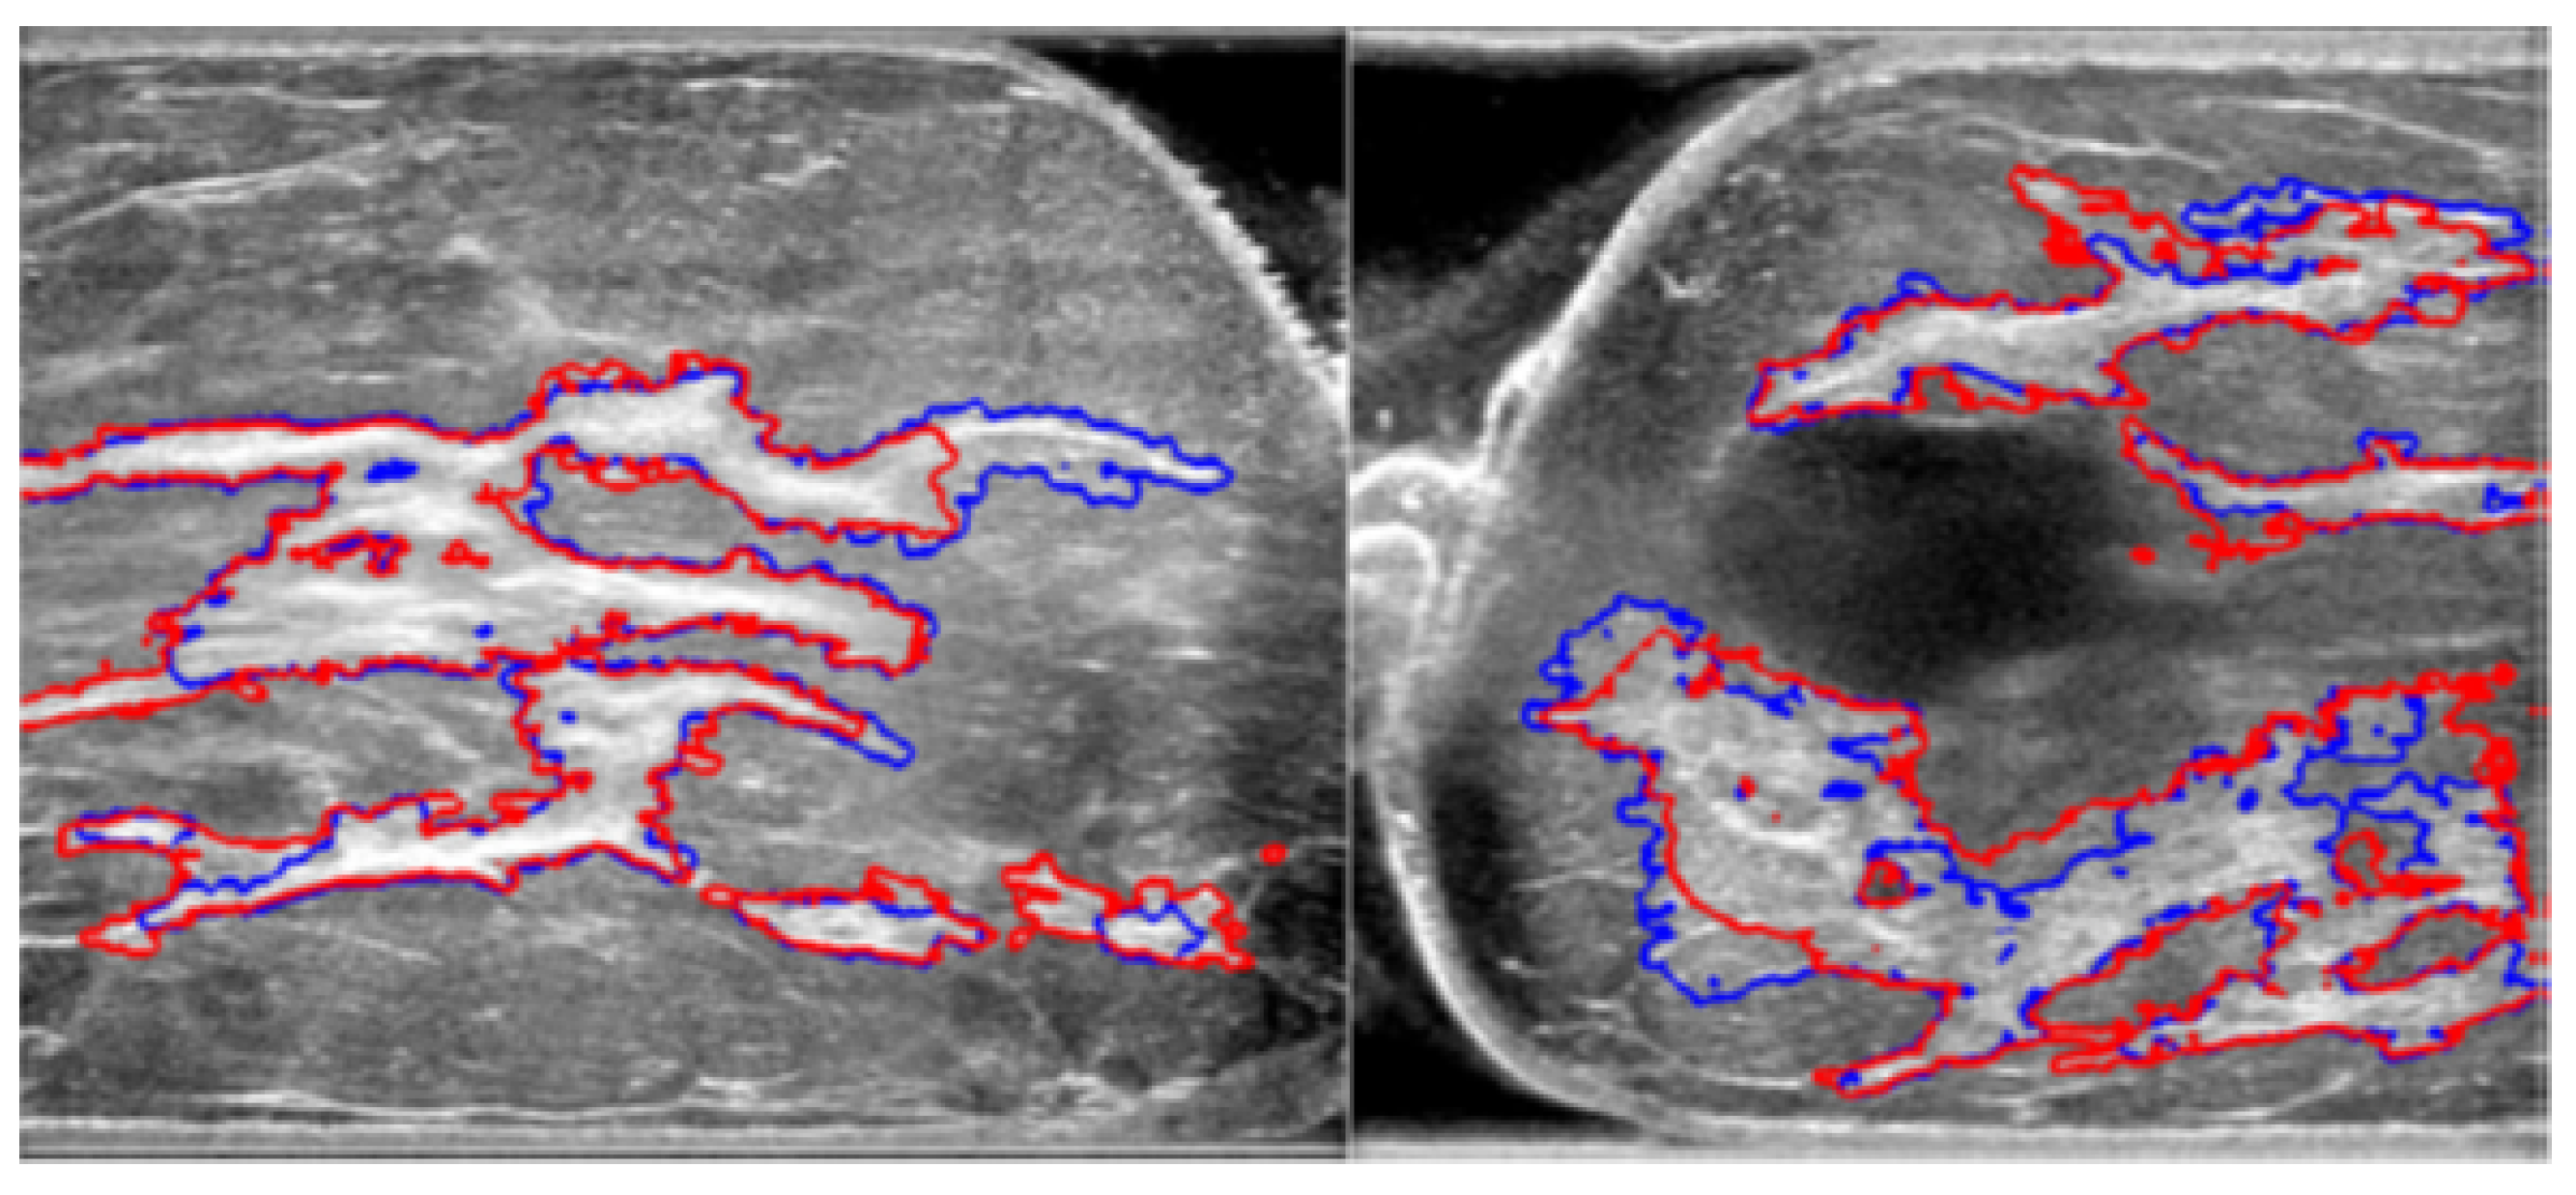

Automated segmentation shows good congruence with manual segmentation while conserving detailed structures; a sample comparison diagram is shown in Figure 8. The red contours are from manual segmentation, and the blue contours are from automated segmentation.

Figure 8.

Comparison of manual and automated segmentation of fibroglandular tissues [17].

Experimental results using 21 breast ultrasound cases demonstrated an accuracy of 85.7% and an overlap ratio of 74.54% with manual segmentation. Despite its effectiveness, limitations include challenges with shadow artifact handling, the occasional need for manual correction, and validation on a small dataset. Overall, the automated method shows promise for improving consistency and accuracy in breast cancer diagnosis, but it requires further research to enhance its robustness and applicability.